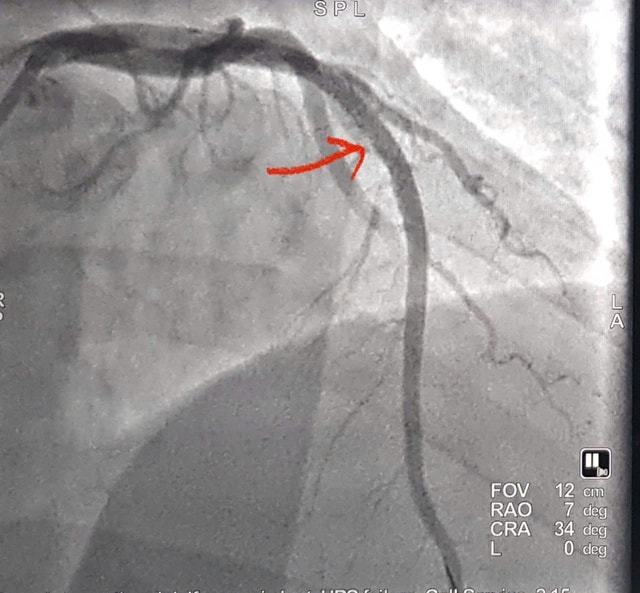

Bệnh nhân lập tức được chỉ định chụp và can thiệp mạch vành qua da bằng hệ thống DSA. Kết quả cho thấy động mạch liên thất trước bị tắc hoàn toàn. Các bác sĩ đã tiến hành nong bóng và đặt stent phủ thuốc, tái thông dòng máu nuôi tim ngay trong quá trình can thiệp.